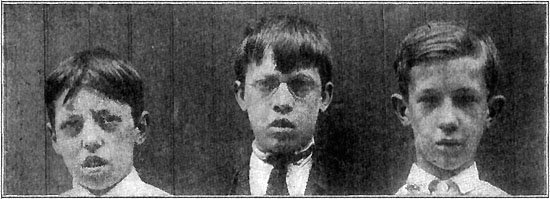

257 Mouth-Breathers